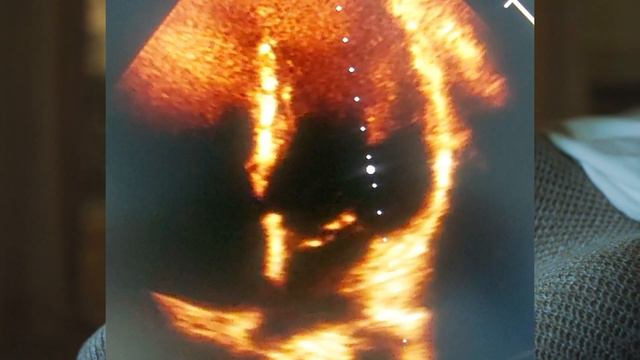

El prolapso valvular mitral ocurre cuando una valva de la válvula mitral es mas laxa prolapsando dentro de la auricula izquierda ocasionando insuficiencia mitral Cardiólogo en managua Nicaragua. Suscribete a Cardiologia Terapia Intensiva ..., видео от 2024-04-22 загрузил на rutube Ответы на Всякое...